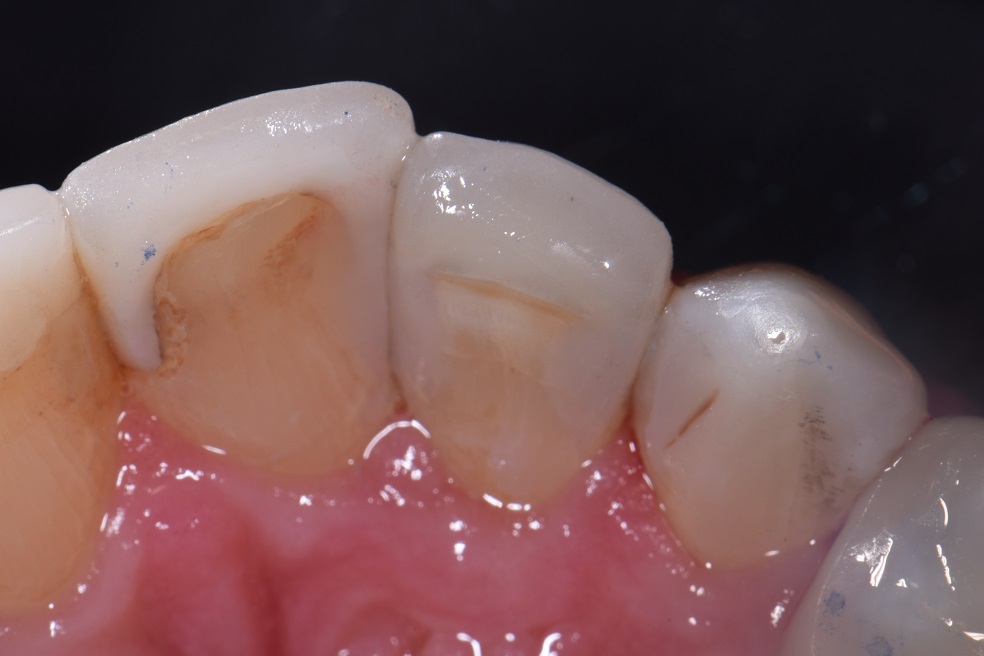

Dental Class 3 Restoration . Preparation outline is determined by the extent of the carious lesion, defects, or old restorative material. It is generally formed with. this paper aims to provide the dentist with practical guidance on the technique for direct composite restoration. dental restoration ranges in price, dependent on what type of restoration you require and which dental clinic you are visiting. in general, the tooth preparation for a class iii direct composite restoration involves (1) obtaining access to the defect (caries,. at first glance, a class iii direct composite restoration can appear to be a fairly routine procedure.